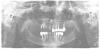

Dio Опубликовано 7 ноября, 2013 Поделиться Опубликовано 7 ноября, 2013 Здравствуйте уважаемые форумчане, около 10 лет назад данной пациентке были установлены имплантаты и сдана работа. интересные факты: имплантат снизу слева был изначально подвижен, врач сказал пройдет, но не прошло, пациентка так и не использует левую сторону в акте жевания (человеческое терпение безгранично ).планируется удаление практически всех зубов и имланатов....... имея опыт переделывания, задумываюсь о преобретения имплантовода для имплантатов 14,15...... может я не прав и зря ищу контакт с производителем, но до этого я всегда использовал для конечного извлечения именно имплантовод. Хирургический и ортопедический этапы были выполнены на юге около 10 лет назад. О том какая система стоит узнали от пациентки. Заранее спс за помощь. Ссылка на комментарий